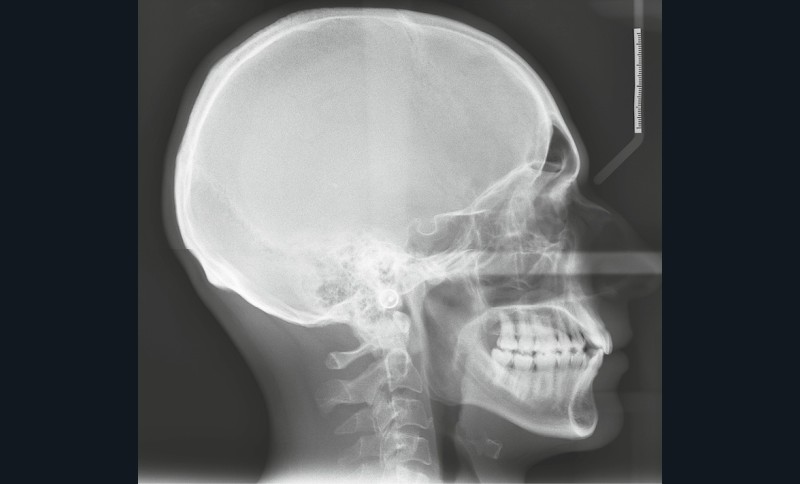

Diagnostic (fig. 1a-i)

Le patient consulte initialement pour des défauts d’alignement. L’examen clinique confirme l’existence d’un encombrement antérieur bimaxillaire, mais révèle aussi la présence d’une Classe II dentaire sévère, d’une exoclusion de la 27 et de troubles parodontaux (peu ou absence de papilles inter-dentaires). Sur le plan squelettique, le patient est relativement équilibré avec un profil harmonieux.